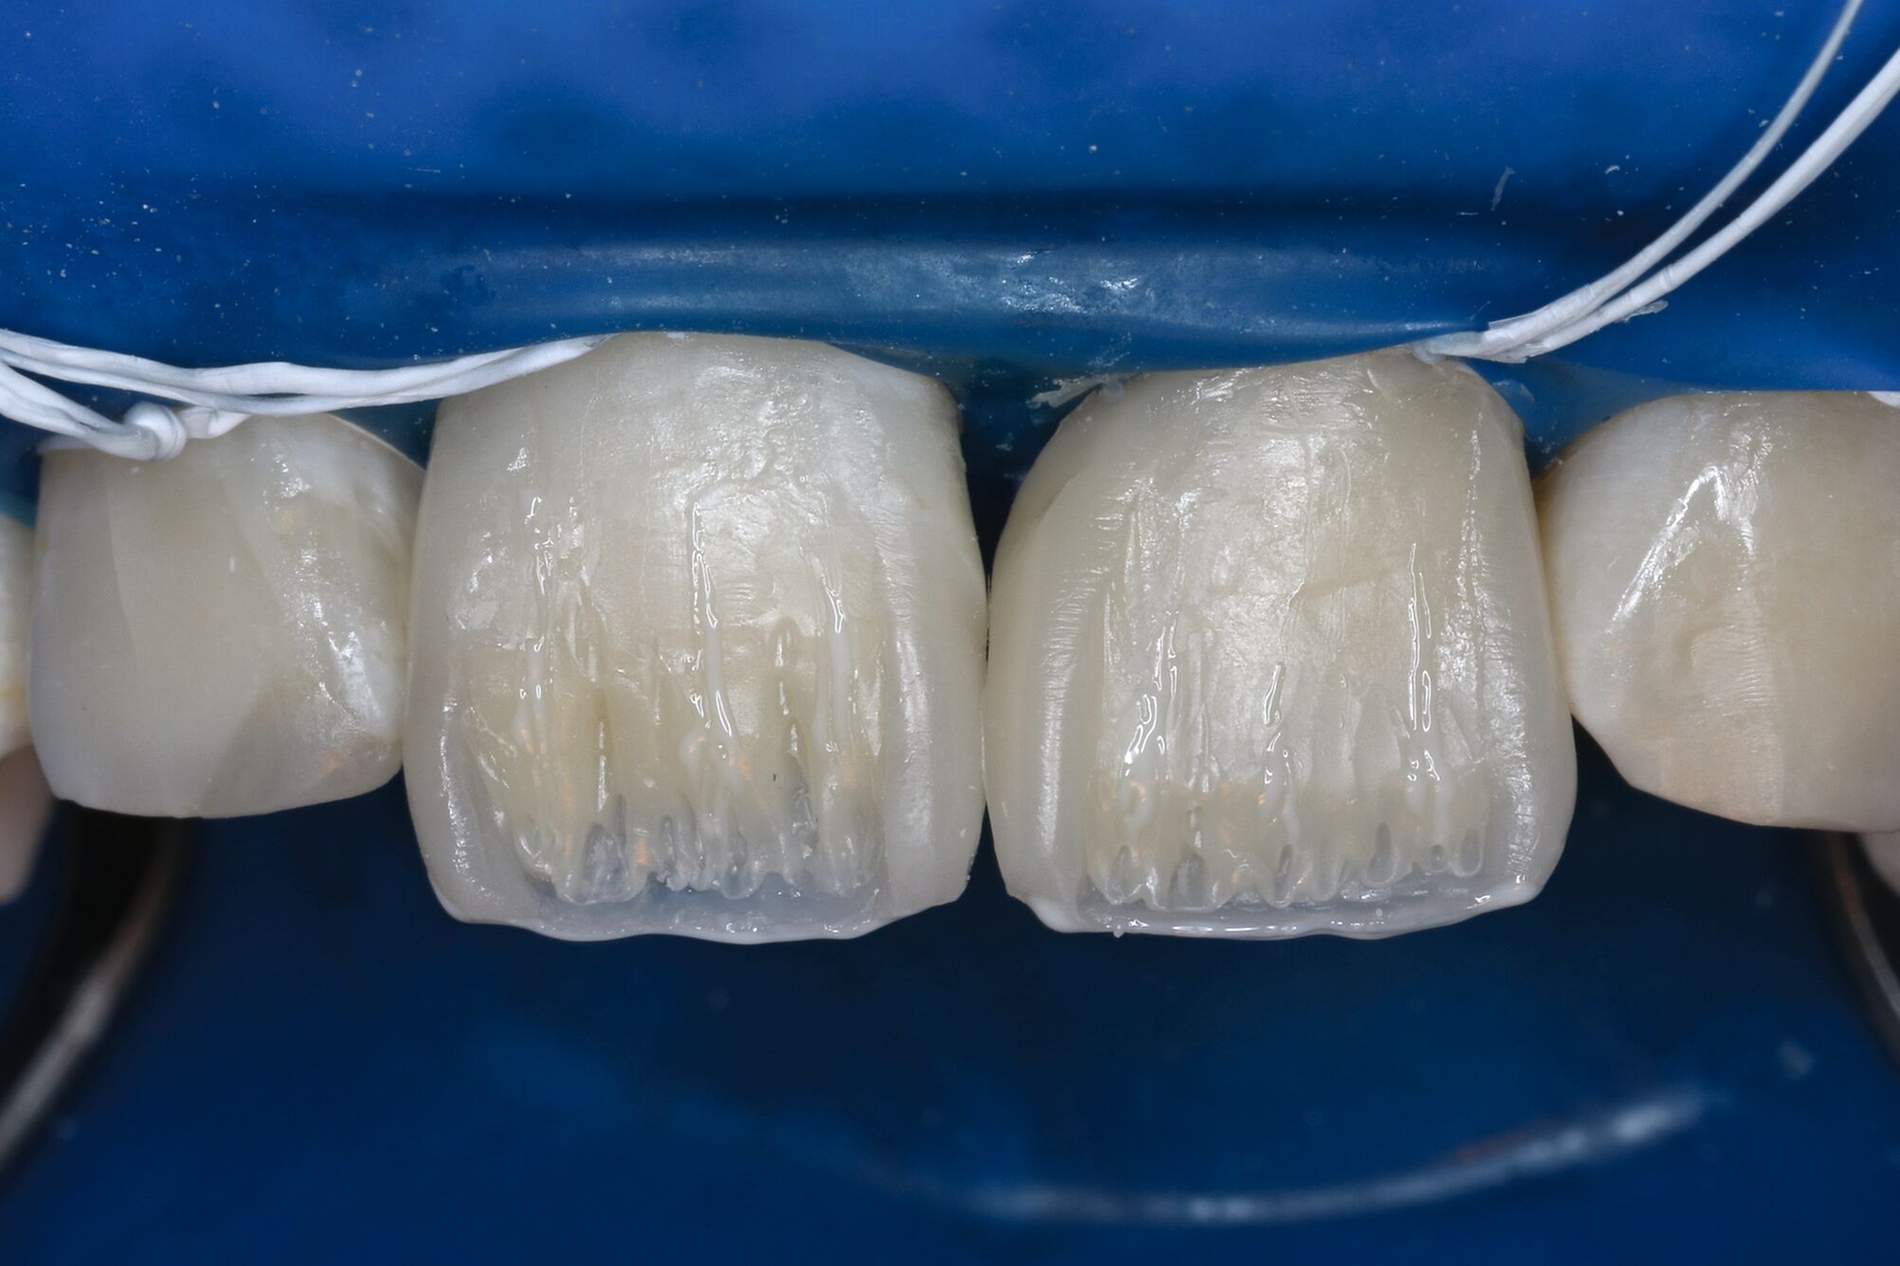

Restaurative Versorgung nach Zahntransplantation oder nach kieferorthopädischem Lückenschluss

Wenn die Lückenversorgung durch eine Transplantation (siehe Teil 4 der Fortbildung „Dentales Trauma“: Chirurgische Aspekte) oder einen kieferorthopädischen Lückenschluss (siehe Teil 5 der Fortbildung „Dentales Trauma“: Kieferorthopädische Aspekte) vorbereitet wurde, beschränkt sich die restaurative Versorgung auf eine Formkorrektur der Zähne. Diese kann – je nach Situation und Präferenz des Behandlers – mit direkten (Abbildung 4) oder mit (minimalinvasiven) indirekten Restaurationen (Veneers, Teilkronen) erfolgen. Gerade bei jungen Patienten muss allerdings berücksichtigt werden, dass im Zuge der passiven Eruption [Mele et al., 2018] Veränderungen des Gingivaverlaufs an den restaurierten Zähnen zur Exposition der Restaurationsränder führen und eine neue Versorgung nach mehreren Jahren erforderlich machen können.